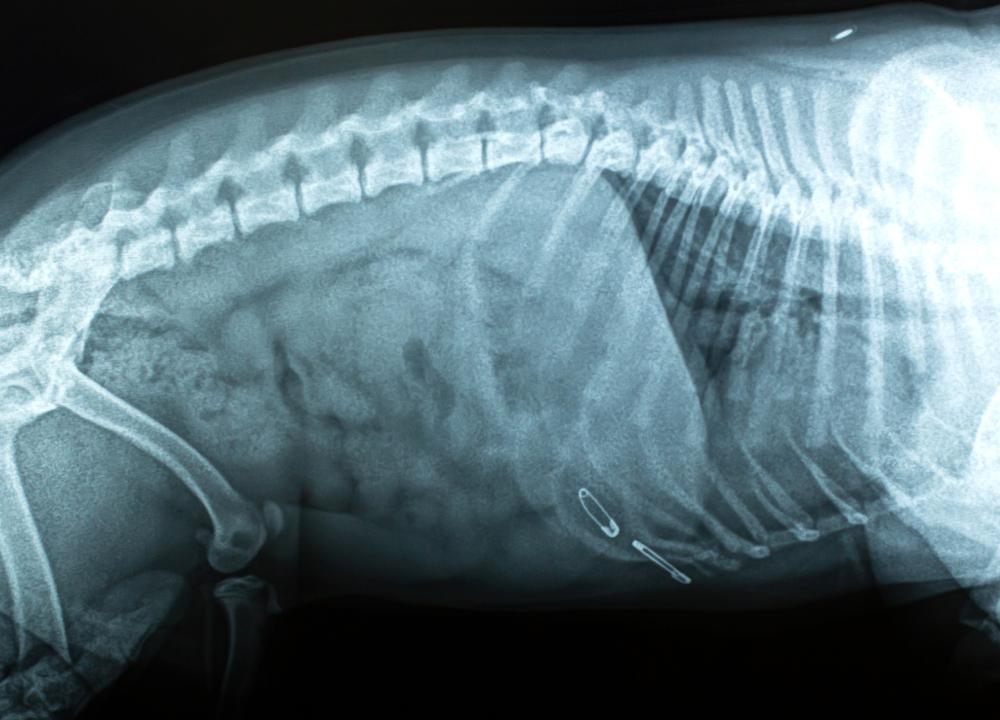

- 如果您的狗吃了可能会卡得更远的尖锐物体。